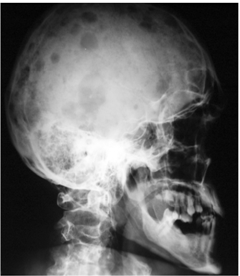

При миеломной болезни поражаются, главным образом, плоские кости (череп, рёбра, таз) и позвонки с резорбцией и остеопорозом с образованием полостей в местах разрастания миеломной ткани по типу (на рентгенограммах) гладкостенных пробоин. Такие изменения могут обнаруживаться кроме плоских костей и в других тканях. [11,12]

Диагностика предполагает полноценное рентгеновское, ядерно-магнитно-резонансное и/или позитронэмиссионное томографическое исследование скелета. Лабораторная и патоморфологическая диагностика основывается на общем анализе крови и мочи (с определением белка Бенс-Джонса), определении белка и белковых фракций сыворотки крови или суточной мочи, уровней иммуноглобулинов сыворотки крови (нефелометрия), аспирационной биопсии костного мозга с подсчетом миелограммы, гистологическом исследовании костного мозга путем трепанобиопсии.